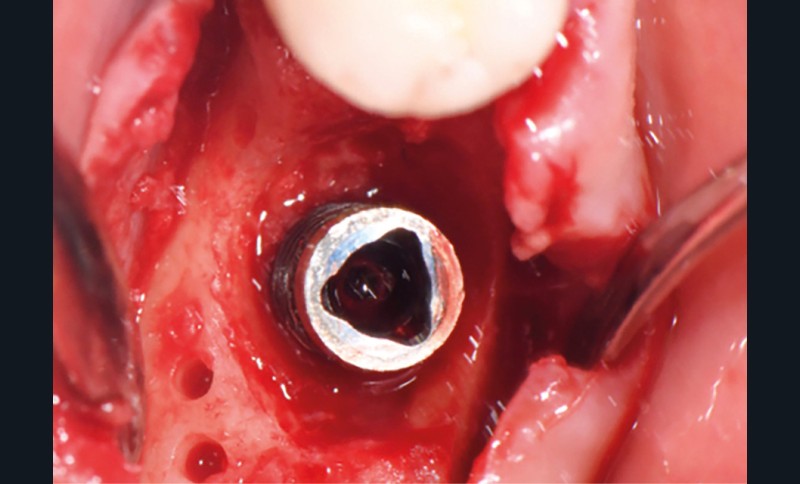

Actes préopératoires

La couronne a été déposée et une vis de couverture mise en place. La patiente a reçu un nettoyage supra-gingival général avec une attention particulière pour l’implant 47, et une irrigation locale avec du gel de chlorhexidine et du peroxyde d’hydrogène pour réduire l’inflammation des tissus. De l’amoxicilline (3 x 500 mg) a été prescrite, à commencer la veille de l’intervention chirurgicale.